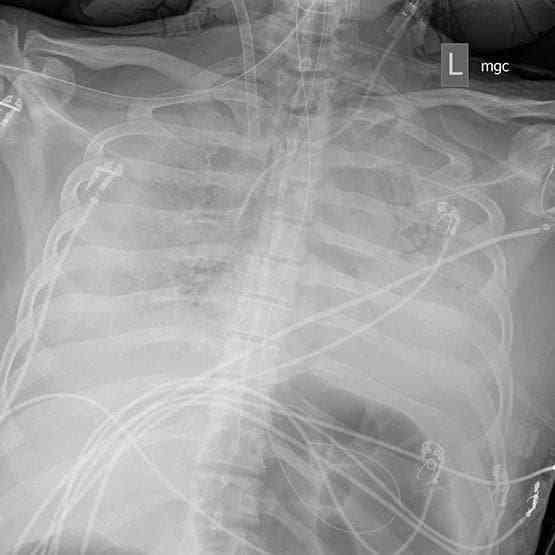

Doctors had given up hope of Jim's survival, according to media reports. Doctors said Jim's lungs were the worst X-rays he had ever seen. Doctors called Jim's wife, Kim, to see her husband.

Within three days, the doctors saw the first ray of hope on an X-ray. On April 14, Jim was removed from the ventilator. Now that he is well, he is back home.